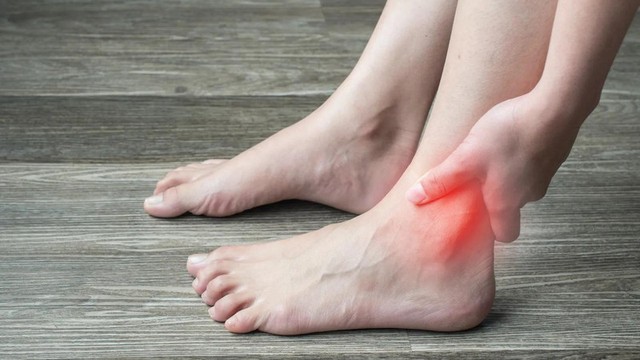

:format(webp)/trat_khop_co_tu_khoi_duoc_khong_7f1c647e70.jpg)

Trật khớp là chấn thương thường xảy ra trong các hoạt động phổ thông xung quanh chúng ta. Đôi khi chỉ từ những hoạt động nhỏ nhưng không đúng tư thế đã có thể dẫn đến trật khớp. Vậy trật khớp có tự khỏi được không?